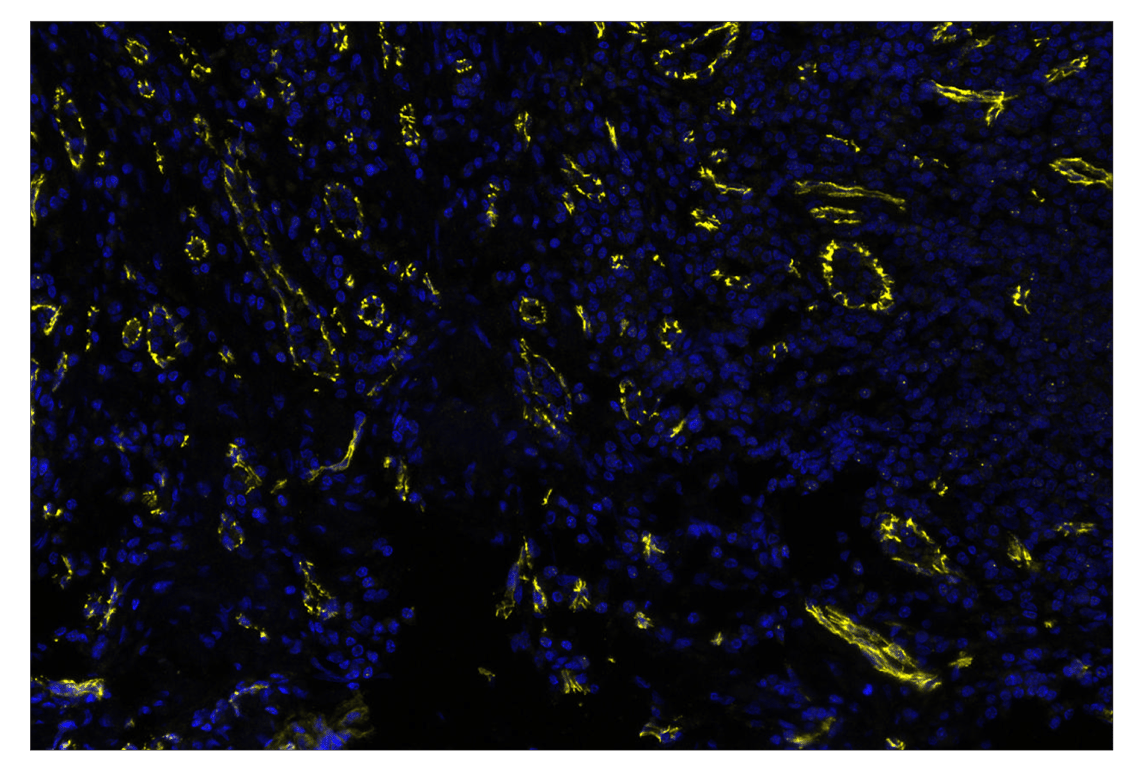

SignalStar™ multiplex immunohistochemical analysis of paraffin-embedded normal human small intestine using VE-Cadherin (E6N7A) & CO-0149-594 SignalStar™ Oligo-Antibody Pair #75963 (yellow) and DAPI #4083 (blue). All fluorophores have been assigned a pseudocolor, as indicated. Staining was performed on the BOND RX autostainer by Leica Biosystems.

Immunohistochemistry Image 2: VE-Cadherin (E6N7A) & CO-0149-647 SignalStar<sup>™</sup> Oligo-Antibody Pair